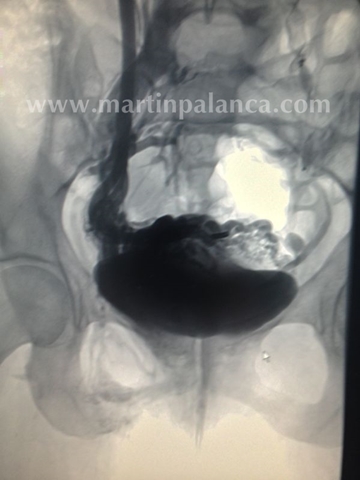

3º)